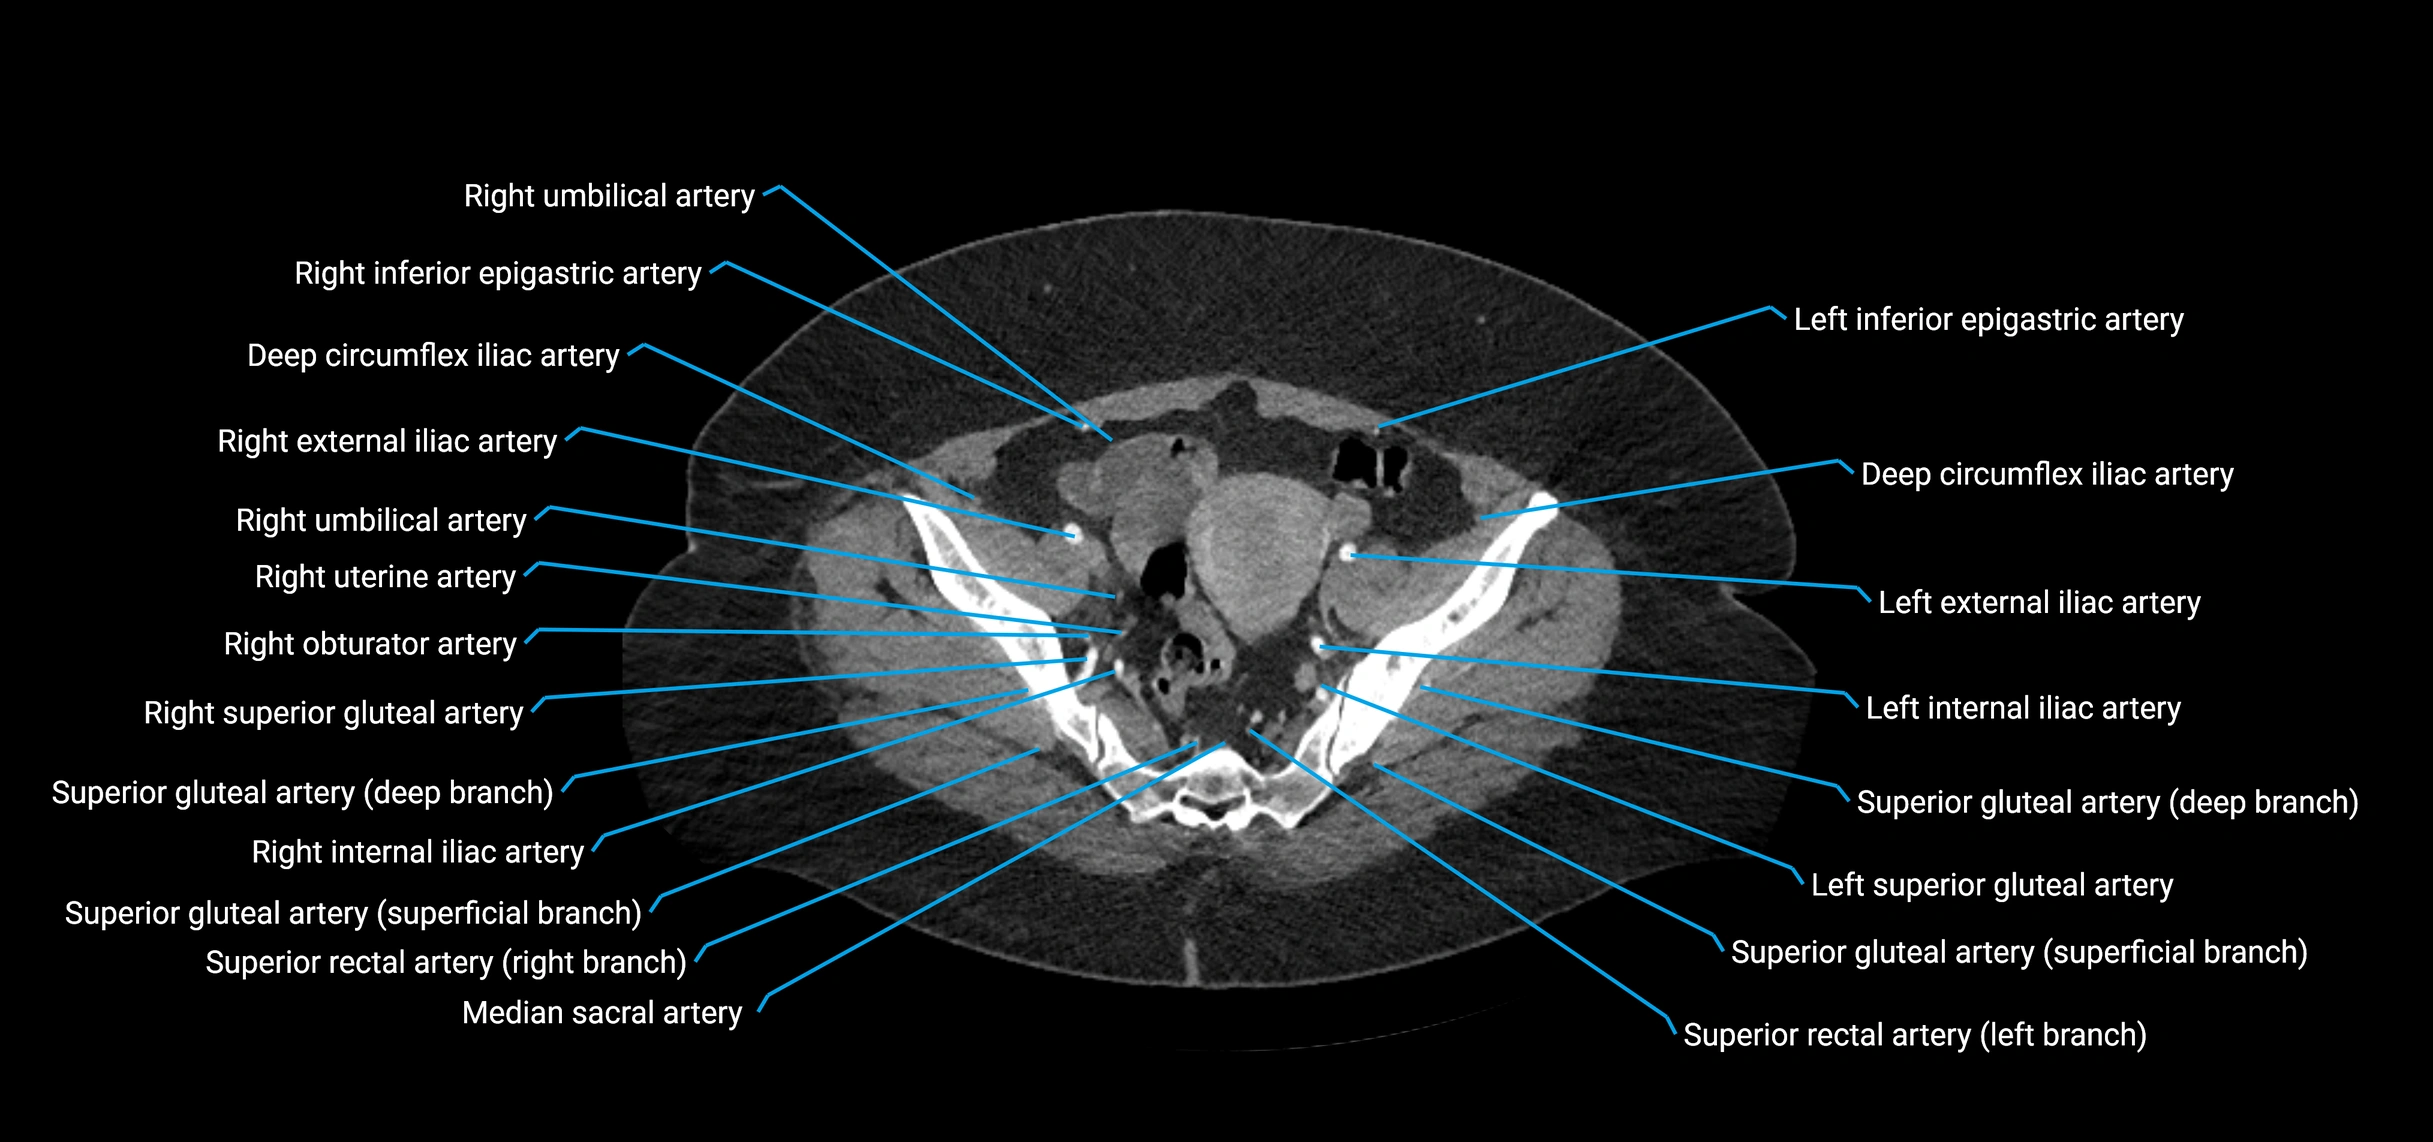

CT images

image

Contrast-enhanced CT (CTA):

• Gold standard for abdominal aortic imaging

• Provides excellent detail of lumen, wall, aneurysm, thrombus, and branch vessels

• Multiplanar and 3D reconstructions help in aneurysm measurement, stent graft planning, and dissection evaluation

• Paired visceral branches: middle suprarenal arteries, renal arteries, gonadal arteries (testicular or ovarian)

• Parietal branches: inferior phrenic arteries, lumbar arteries, median sacral artery

• Terminal branches: right and left common iliac arteries